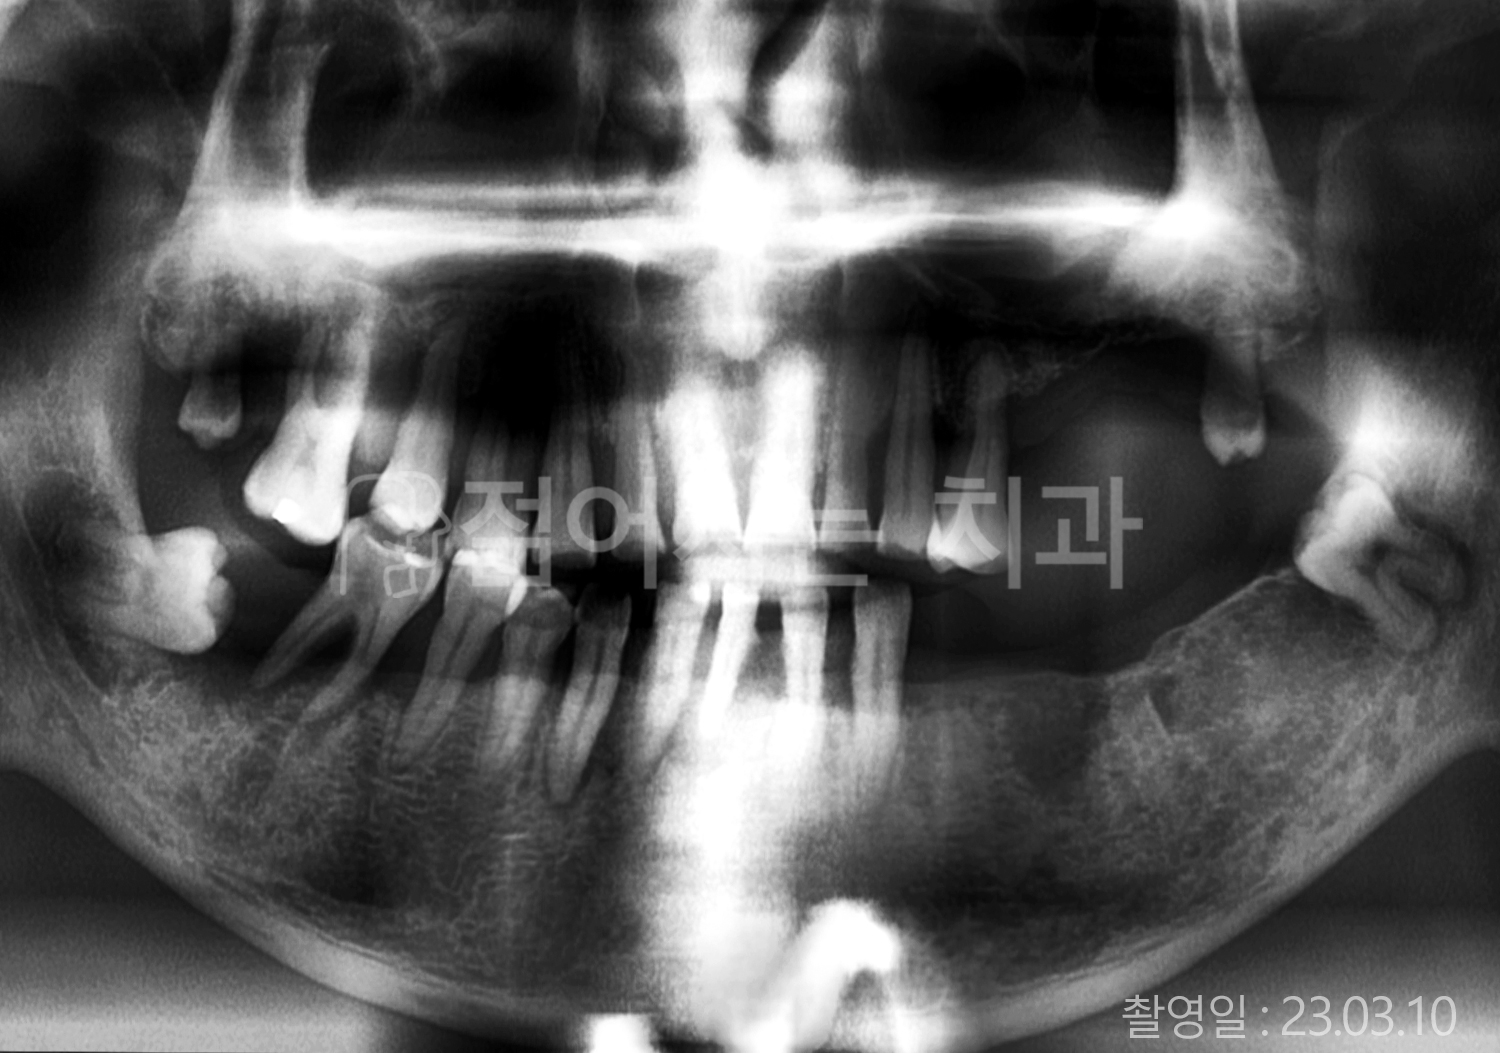

• 80대 전체치아 10개 이상 임플란트

• 60대 고혈압, 당뇨, 고지혈증 전체치아 10개 이상 임플란트

• 60대 전체치아 10개 이상 임플란트

• 60대 고혈압, 고지혈증 전체치아 10개 이상 임플란트

• 50대 고혈압, 당뇨, 고지혈증 전체치아 10개 이상 임플란트

• 70대 골다골증, 파킨스병 전체치아 10개 이상 임플란트

• 40대 전체치아 10개 이상 임플란트

• 60대 골다골증 전체치아 10개 이상 임플란트

• 40대 고혈압 전체치아 10개 이상 임플란트

• 50대 전체치아 10개 이상 임플란트

• 70대 전체치아 10개 이상 임플란트